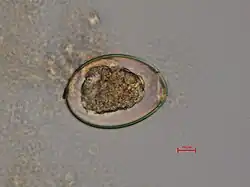

D. latum tiene un escólex alargado y, a diferencia de otros cestodos, tiene discos succionadores en lugar de ventosas. Los huevos son ovales y tienen un opérculo en forma de tapa.

Demostración de huevos con opérculo en las evacuaciones o proglótides que son más anchas que alargadas (con patrón en roseta de las ramas uterinas) en heces o vómito.